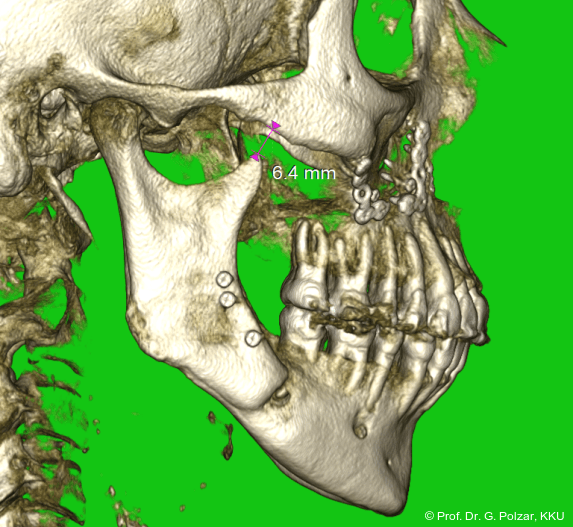

Im Sagittalschnitt zeigen beide Kiefergelenke eine deutlich anteriore Position. Der dorsokraniale Abstand betrug rechts 7,0 mm und links 5,8 mm. In der PEP waren sie im lateralen Bereich ca. 1 mm kleiner als in der Mitte der Sagittalprojektion (Abb. 6a–d).

Diese deutlich anteriore Gelenkposition im Neutralbiss ließ den Verdacht auf einen Sunday Bite zu. Das heißt, die Patientin schob den Unterkiefer aktiv nach vorne, um damit schönere Schneidezahnkontakte bzw. eine vermeintlich neutrale Okklusion zu erreichen. Nach mühsamen Lockerungsübungen gelang es der Patientin, auch in die zen­trale Kiefergelenkposition zu wechseln. So zeigte sich das ganze Ausmaß der Malokklusion. In neutraler KG-Position hatte die Patientin eine sagittale Frontzahnstufe von ca. 7 mm mit 1 PB Klasse II-Okklusion im Seitenzahn­bereich (Abb.5a+b, 7a–c).